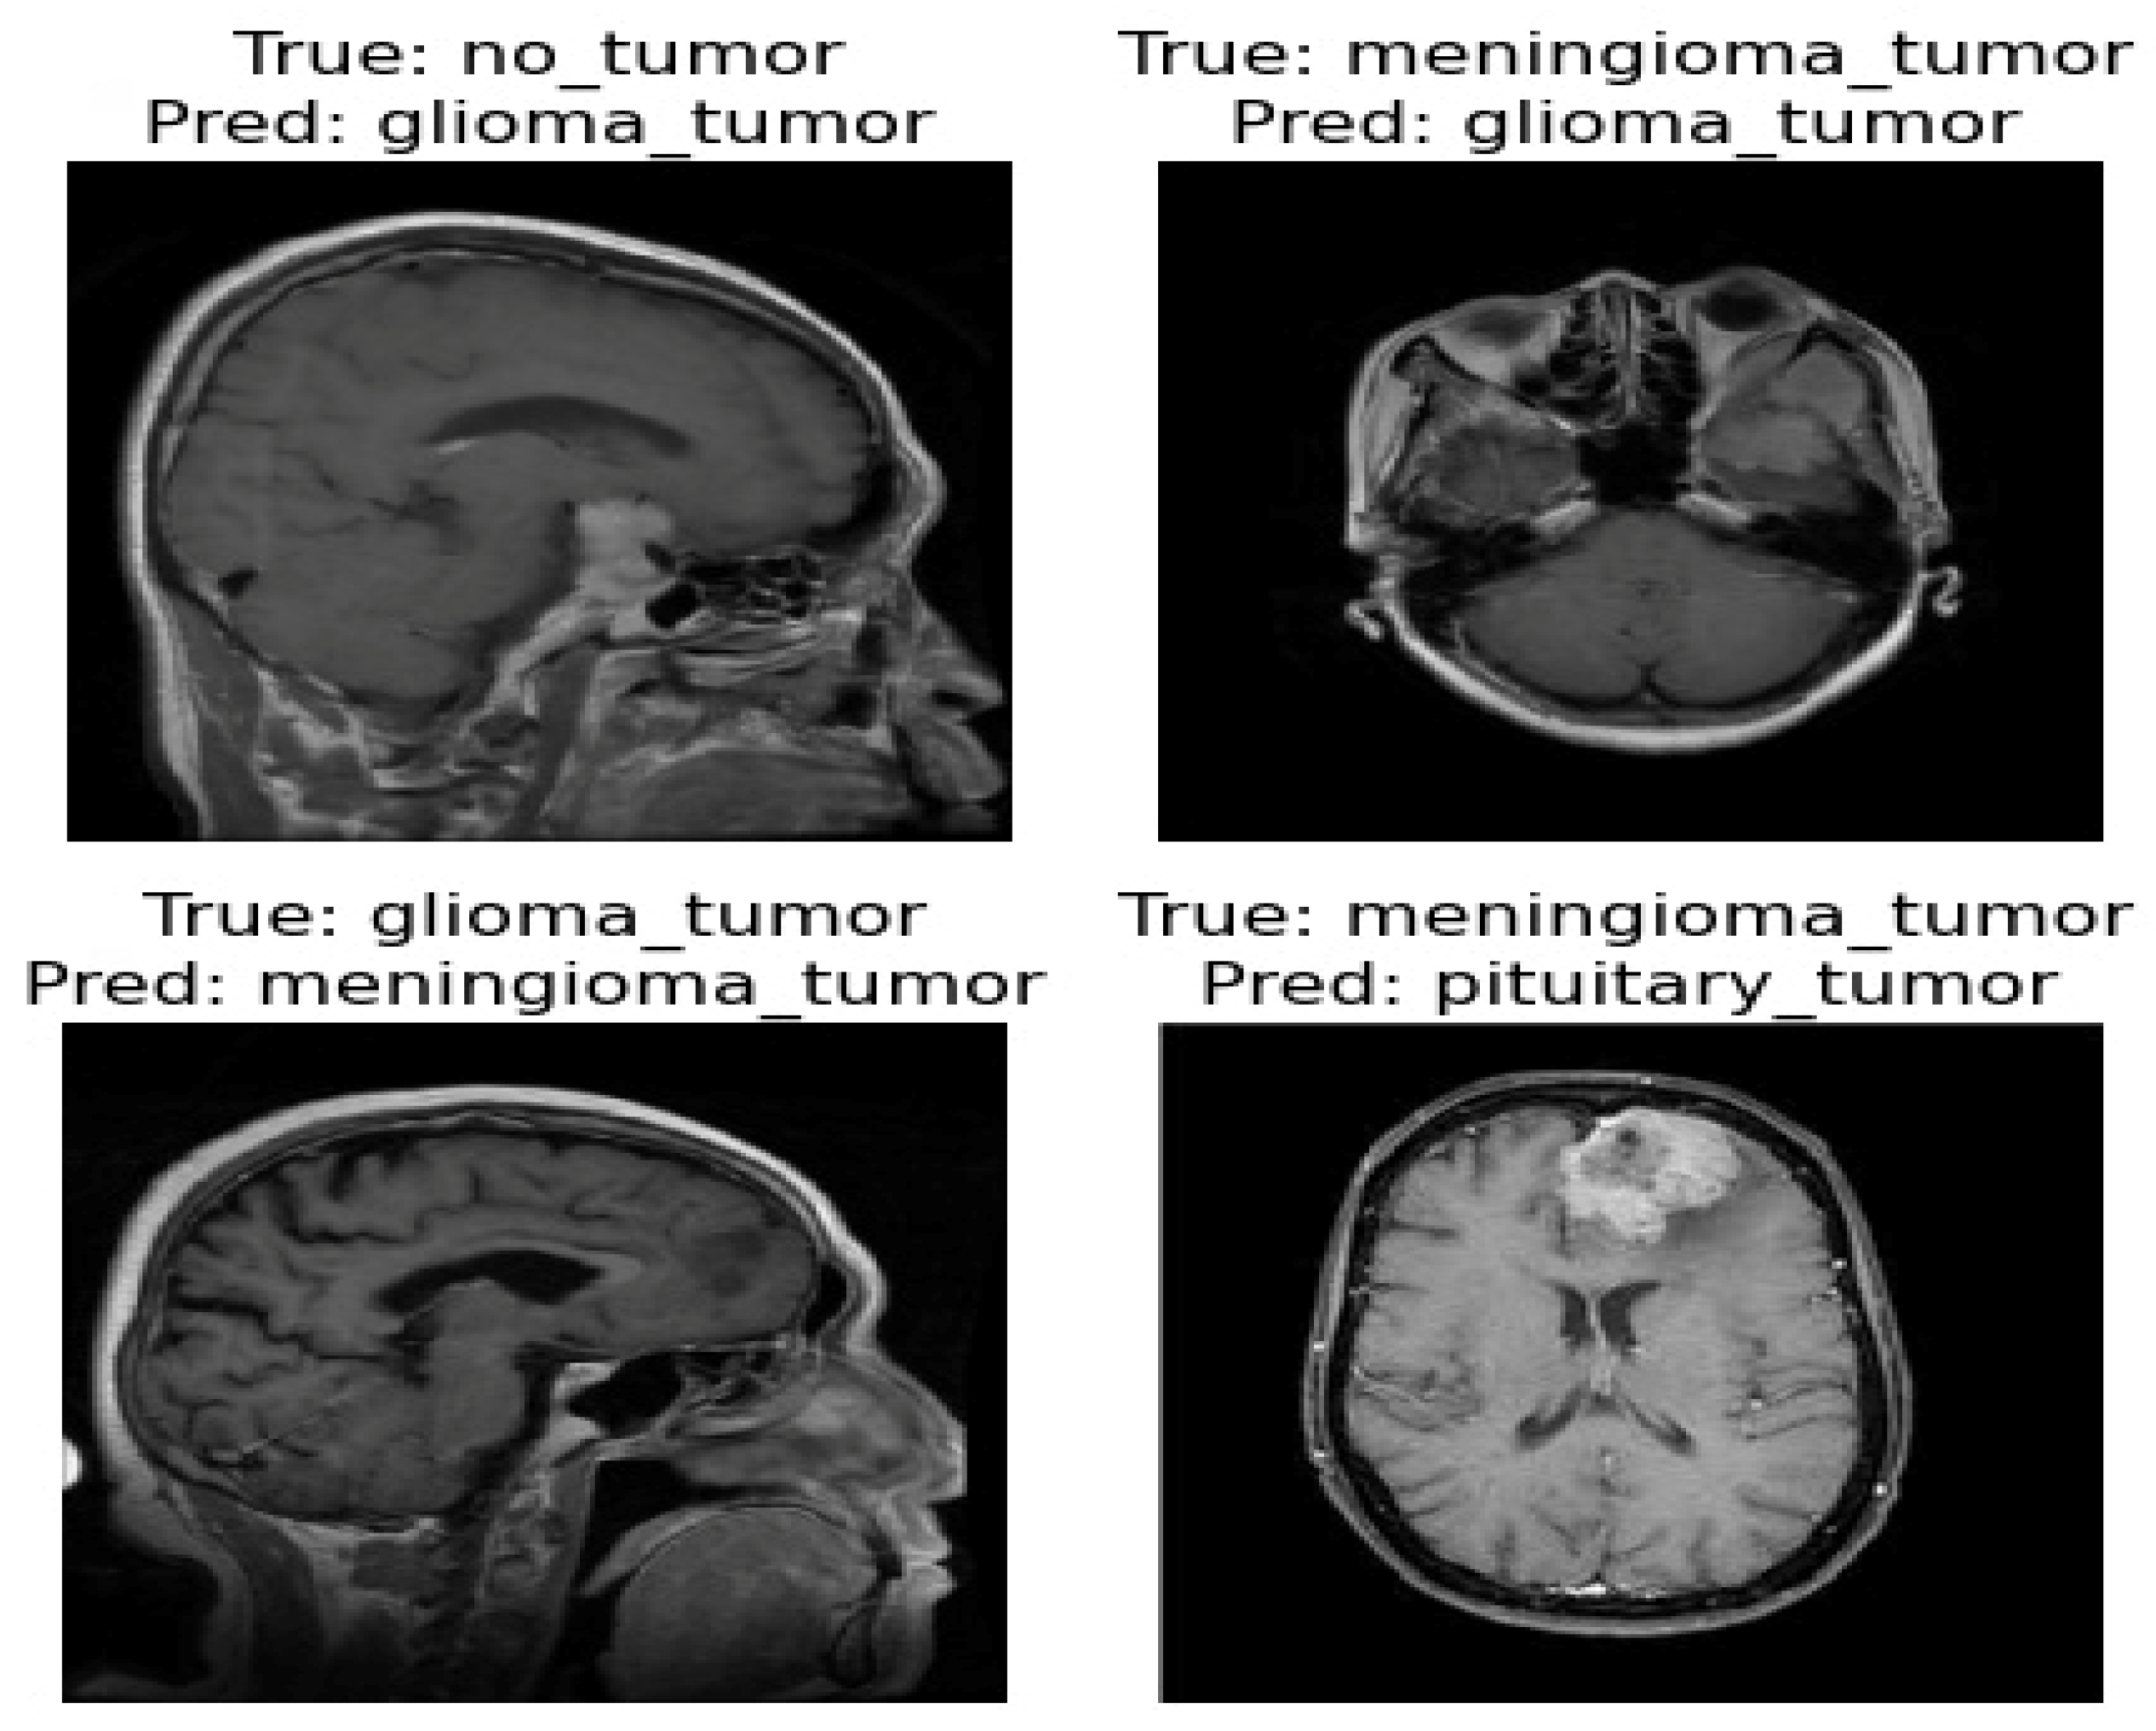

The confusion matrix was utilized to provide additional insights into the model’s performance by summarizing the correctly and incorrectly classified instances. For the validation set of 857 images, the model correctly identified 841 images, while 16 images were misclassified as shown in Figure 4. Furthermore, Figure 5 and Figure 6 present the classification outcomes of the proposed study, illustrating both accurate and inaccurate classifications.

Figure 5.

Figure 6.

Incorrect classification result of proposed ViT model.

Figure 5 and Figure 6 present the visual results obtained from our FT-ViT model. These figures serve as compelling evidence of the model’s efficacy in accurately classifying different tumor types. As depicted in Figure 5, the proposed FT-ViT model exhibits remarkable performance, achieving an impressive accuracy of 98.13%. The high accuracy underscores the model’s capability to correctly identify tumor types with exceptional precision. However, there are instances where the FT-ViT model encounters challenges in accurately classifying tumor types. These instances are also reflected in the confusion matrix, which highlights the cases where the model misclassified tumor types. Figure 6 provides a visual representation of the results where the FT-ViT model encountered difficulties and failed to identify certain tumors accurately. The incorporation of both Figure 5 and Figure 6 allows us to comprehensively evaluate the FT-ViT model, highlighting its overall success in tumor classification, while also shedding light on areas for improvement.